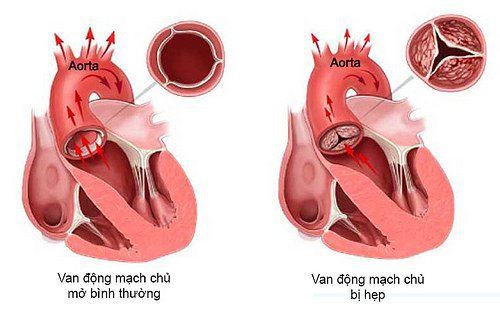

1. Động mạch chủ là gì?

Động mạch chủ là động mạch lớn nhất trong cơ thể. Chúng có chức năng dẫn máu từ tim đến các cơ quan trong cơ thể. Về cơ bản, động mạch chủ có thể chia thành 5 đoạn, bao gồm: gốc động mạch chủ, động mạch chủ ngực lên, quai động mạch chủ, động mạch chủ ngực xuống và động mạch chủ bụng.

- Bệnh nhân mắc các bệnh như: hẹp động mạch, phình động mạch, thông động tĩnh mạch, u mạch, kém phát triển mạch...

- Bệnh nhân bị thiếu máu não, bác sĩ nghi ngờ cần kiểm tra có hẹp hay bất thường động mạch chủ không